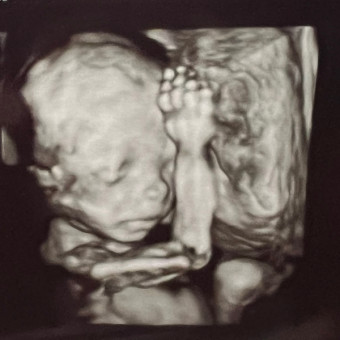

Melanie & Kyle Gabriel

June 25, 2026